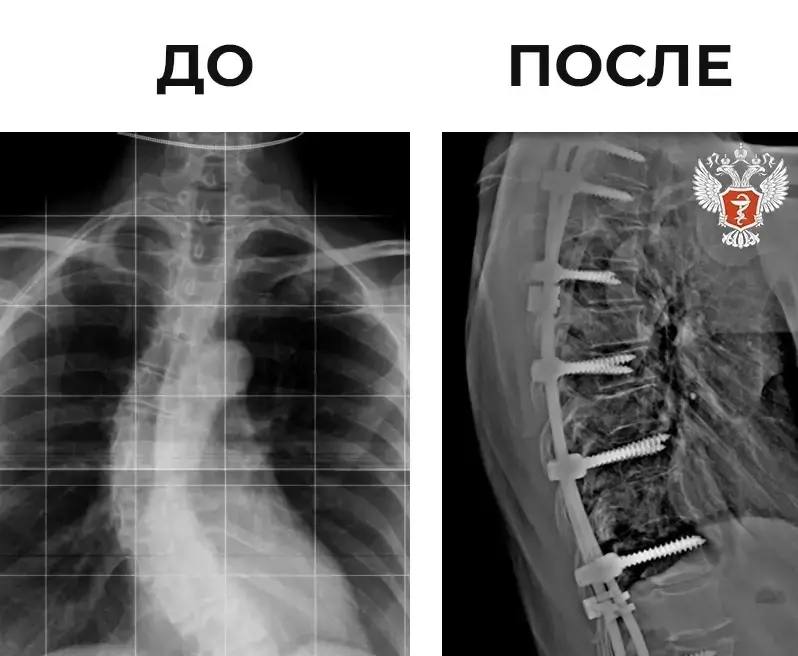

В ходе вмешательства пациентке установили 18-винтовую металлоконструкцию для коррекции и фиксации позвоночника в правильном положении.